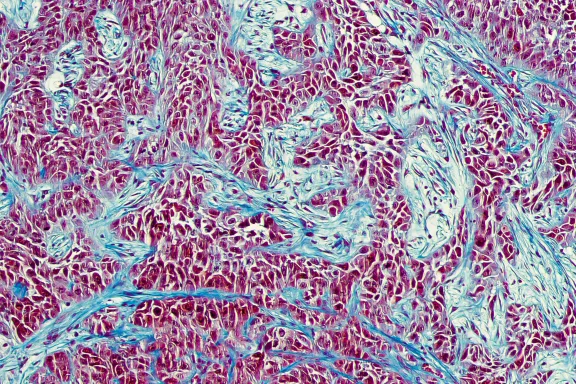

Salvador Aznar Benitah a pu établir une relation directe entre la consommation de certaines graisses et la formation de métastases. En étudiant le comportement de ces cellules, Salvador Aznar Benitah a mis en évidence qu’une alimentation trop riche en graisses saturées est un facteur de risque avéré, non seulement pour la santé, mais aussi pour la progression du cancer.

Ses travaux lui ont permis d’identifier un marqueur protéique qui pourrait jouer un rôle dans l’absorption des graisses, et donc avoir un impact sur la prolifération des cellules cancéreuses. Le chercheur a ainsi démontré qu'un bon équilibre alimentaire permet de contenir la progression des tumeurs, mais aussi simplement de retarder le vieillissement des cellules.